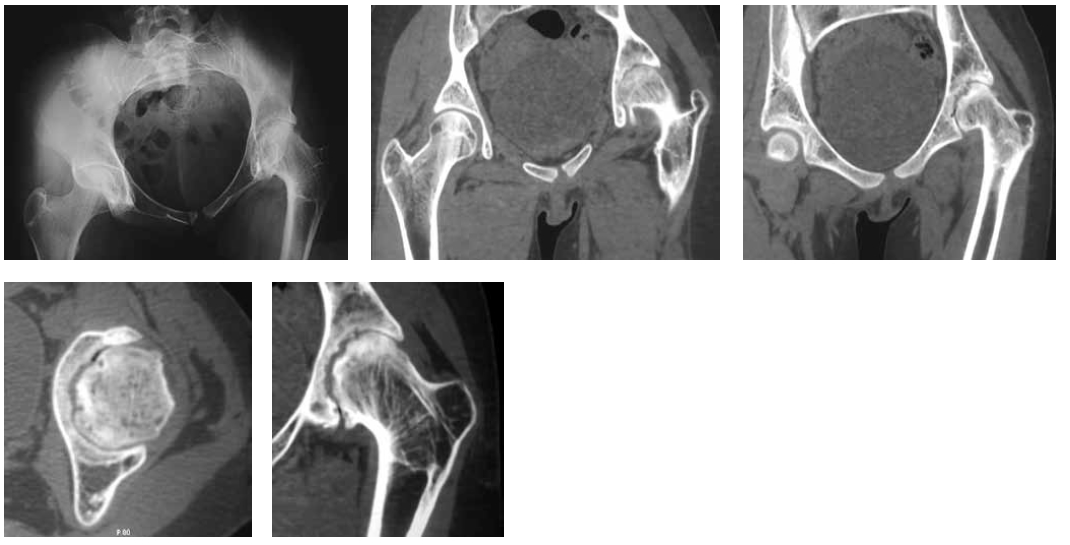

Radiography and computed tomography of the hip joints (Fig. 2) showed that on the left, the femoral head was deformed and had an irregular shape and uneven contour. The contour of the acetabulum was uneven. The joint gap was sharply narrowed and was not traced in some places. The diagnosis was a consequence of septic coxitis, secondary deforming coxatrosis on the left, and fibrous ankylosis of the left hip joint. Considering the clinical and radiological picture, the pronounced vicious position of the lower limb, the absence of pain syndrome, and early adolescence, we decided to conduct a stepwise organ-preserving complex treatment aimed at eliminating the vicious position of the limb by eliminating the fibrous block between the articular surfaces with subsequent development of movements in the hip joint. The treatment plan included a combination of the following modern methods: distraction in the device, arthroscopy, intra-articular injections, therapeutic exercises and other rehabilitation measures. The first stage (Fig. 3) for the expansion of the joint space involved the imposition of a wire-rod distraction apparatus of the MKC on the pelvic bone and the left hip with spinal adductomy.

Fig. 2. Radiograph and computed tomography (CT) scan of the hip joints. Deforming coxatrosis. The femoral head is deformed, has an irregular shape, and has an uneven contour. The cotyloid cavity also has an uneven contour. Joint space is sharply narrowed and is wavy because of the closure of the articular surfaces of the head and cavity of “puzzle” type. Degenerative-dystrophic changes in the form of areas of subchondral sclerosis, cystic changes, and marginal bone growths. Adduction contracture at an angle of 40°